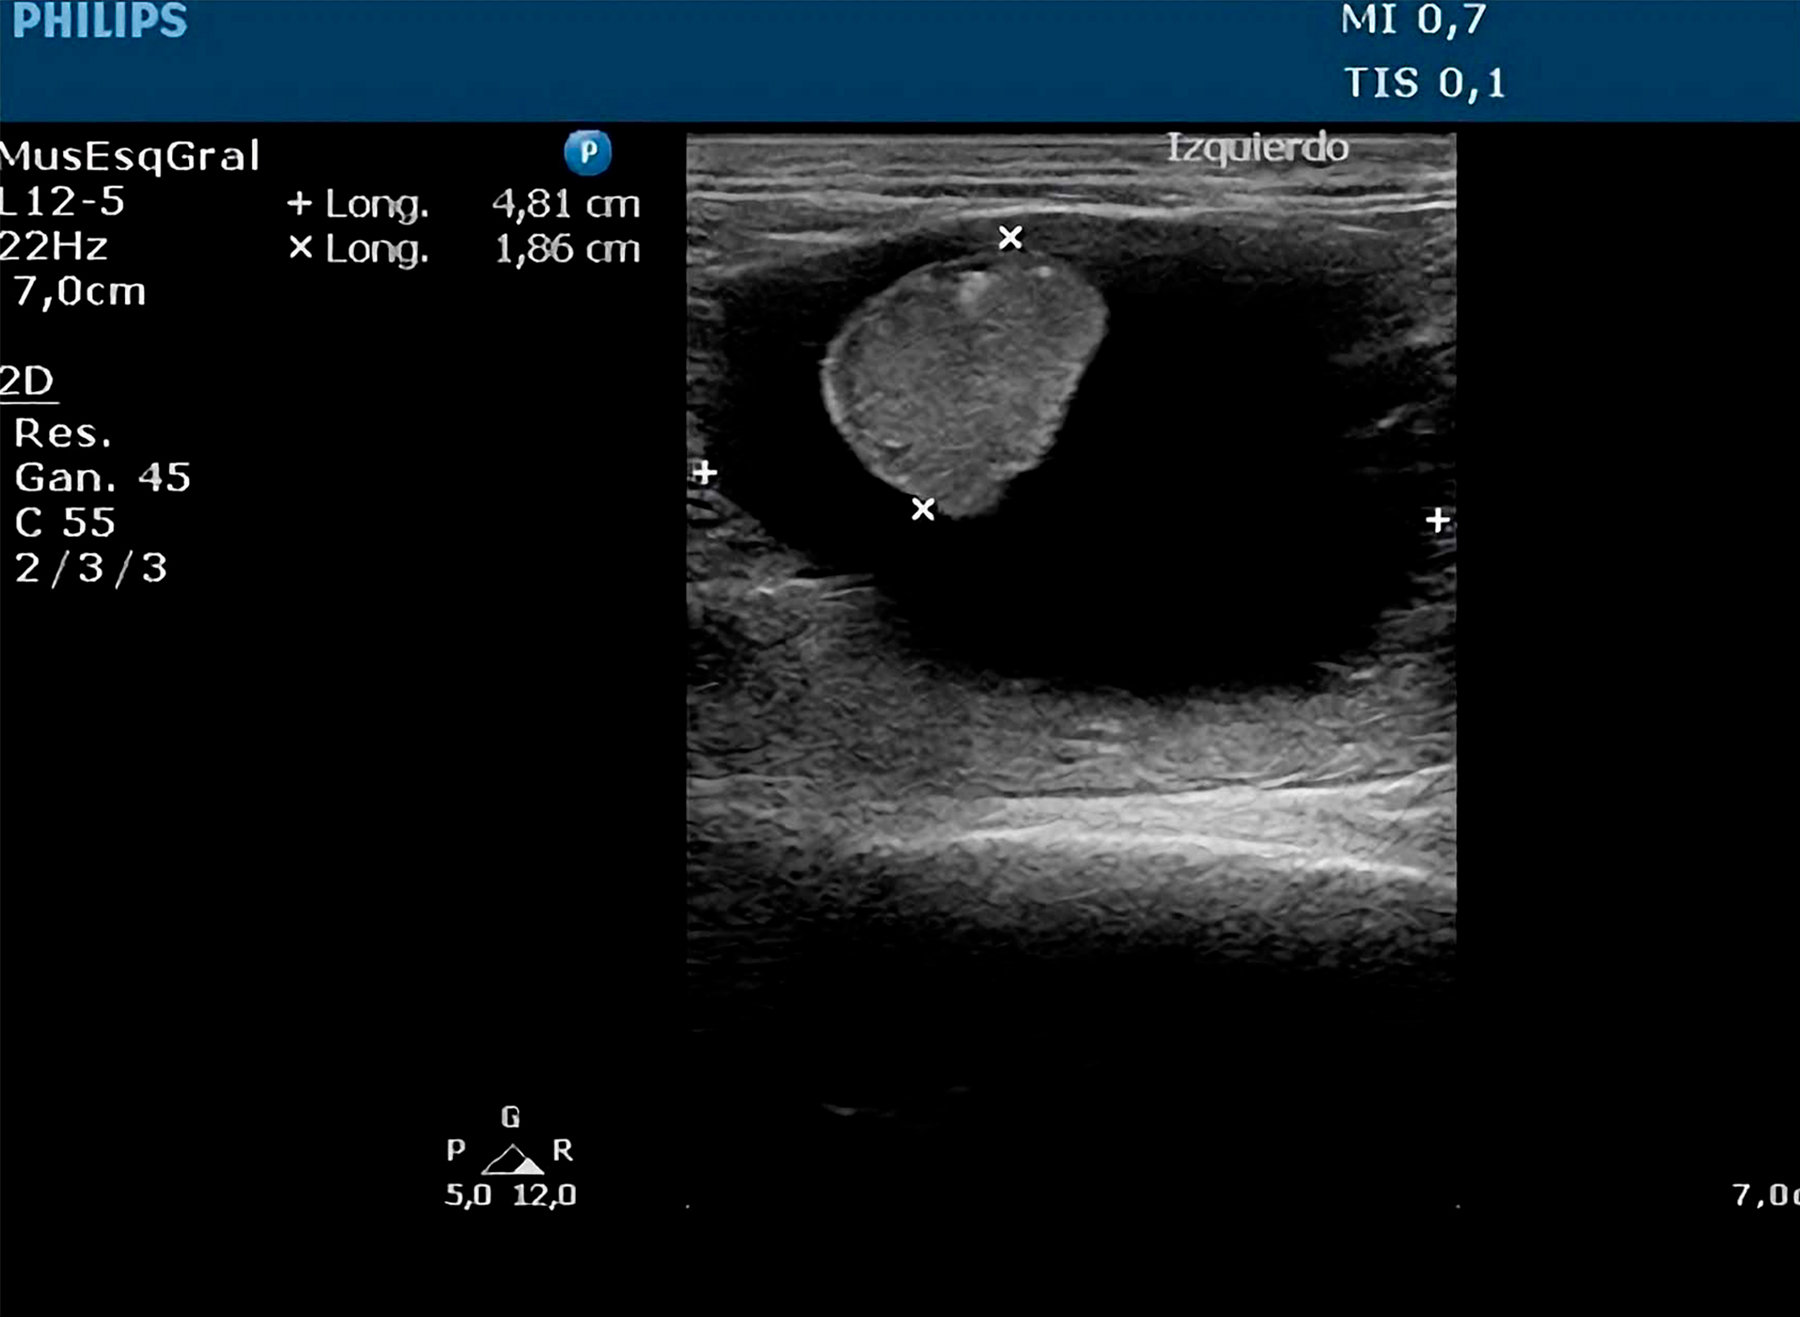

Hallazgos Ecográficos:

Se evidenció atrofia renal asociada a efusión perirrenal en uno de los órganos, mientras que el riñón contralateral presentó morfología y ecogenicidad conservadas.

Se realizó nefrectomía del riñón afectado. Tras 72 horas de hospitalización con soporte fluidoterápico, el paciente experimentó una evolución postoperatoria favorable con recuperación clínica satisfactoria.